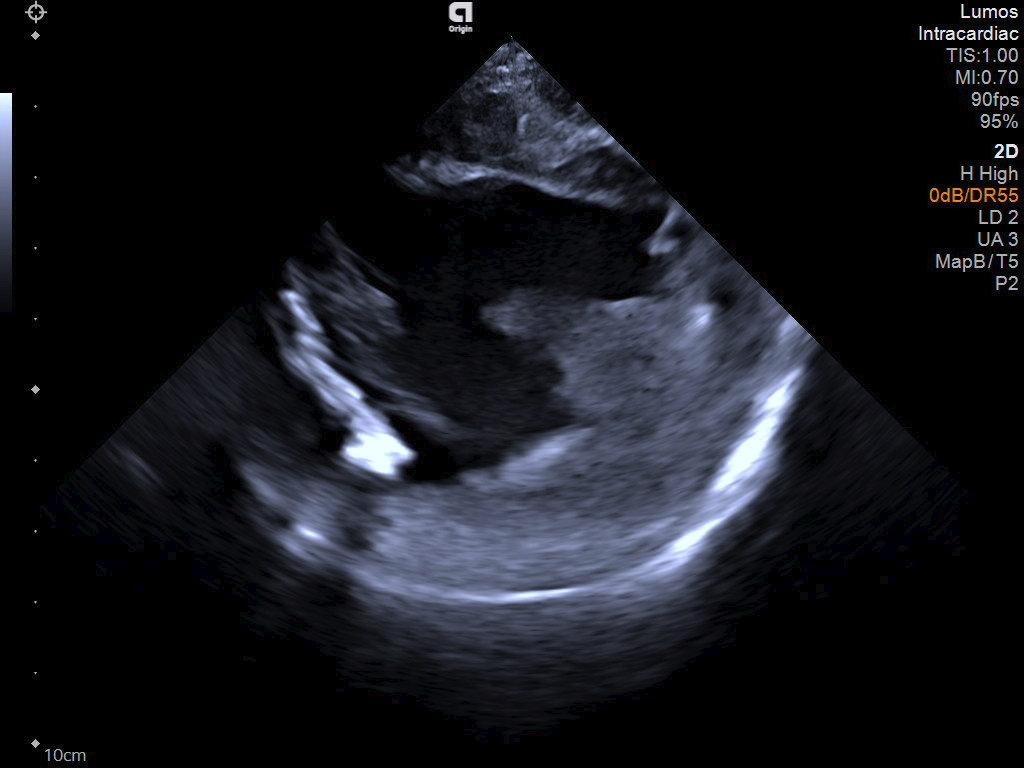

2D LV with ablation catheter

Left ventricle with ablation catheter visualization